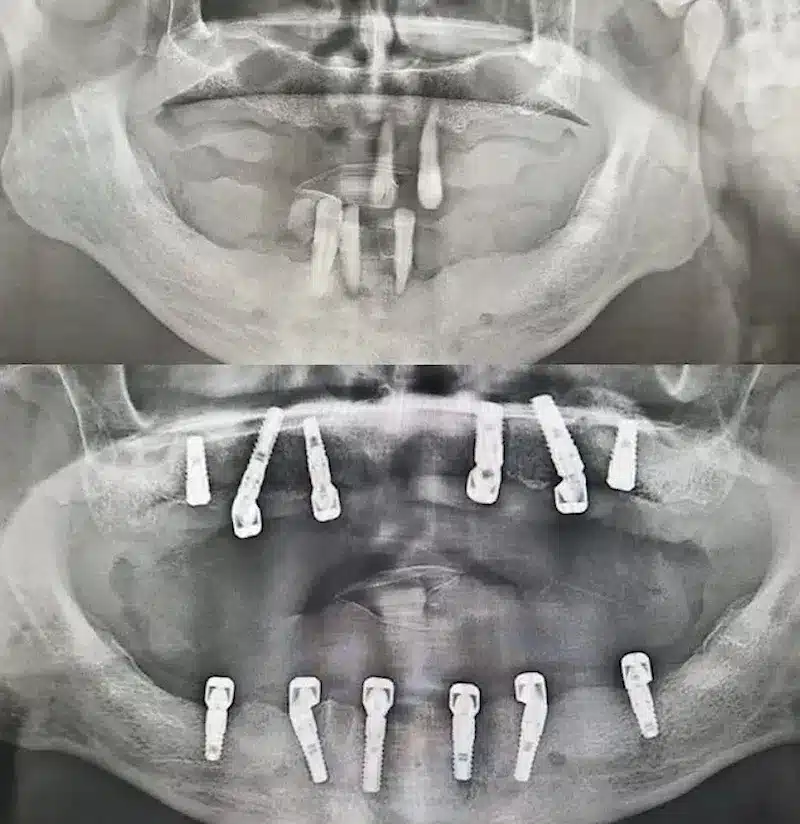

Dr. Seden Aksu is a specialist in modern implantology and surgical dentistry with extensive experience in the management of complex clinical cases. In her practice, she applies comprehensive surgical planning, minimally invasive techniques, and advanced regenerative technologies aimed at restoring both the function of the dentoalveolar system and the aesthetics of the smile. Dr. Aksu has significant experience in performing implant procedures, bone augmentation, and periodontal surgery, including the treatment of patients with severe bone loss. The primary goal of her work is to achieve stable, long-term outcomes in implant rehabilitation and the restoration of oral tissue health.